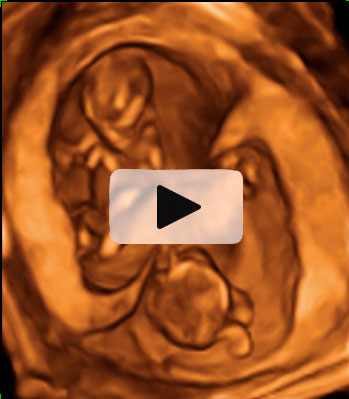

El movimiento de gemelos en el útero encierra sorpresas, como en esta ecografía 4D en la que vemos a dos hermanos en sus respectivas bolsas. El gemelo de la derecha parece estar bailando el "hula hoop" con su propio cordón umbilical, que le rodea las piernas formando un círculo. Destaca la posición casi erguida del niño dentro del útero materno, casi a punto de dar un paso. Cuando uno de los fetos genera mucho movimiento, suele arrastrar a su gemelo a que se mueva también, aunque esté adormecido.

Ecografía 4D de gemelos de 12 semanas moviéndose: el baile del "hula hoop"